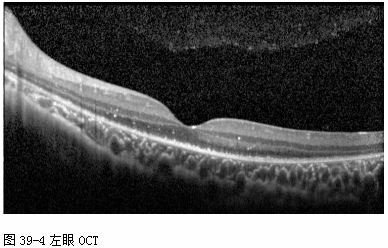

OCT(2012-7-31,本院): 双眼后极视网膜各层高反射点,IS/OS和ELM消失, RPE较毛糙。(见图39-3和图39-4)

FFA(2013-7-31,本院): 双眼视网膜动静脉充盈时间正常范围,视网膜后极和中周荧光轻度渗漏, 视乳头荧光渗漏,边界模糊——考虑“双眼葡萄膜炎? ”(见图39-5)